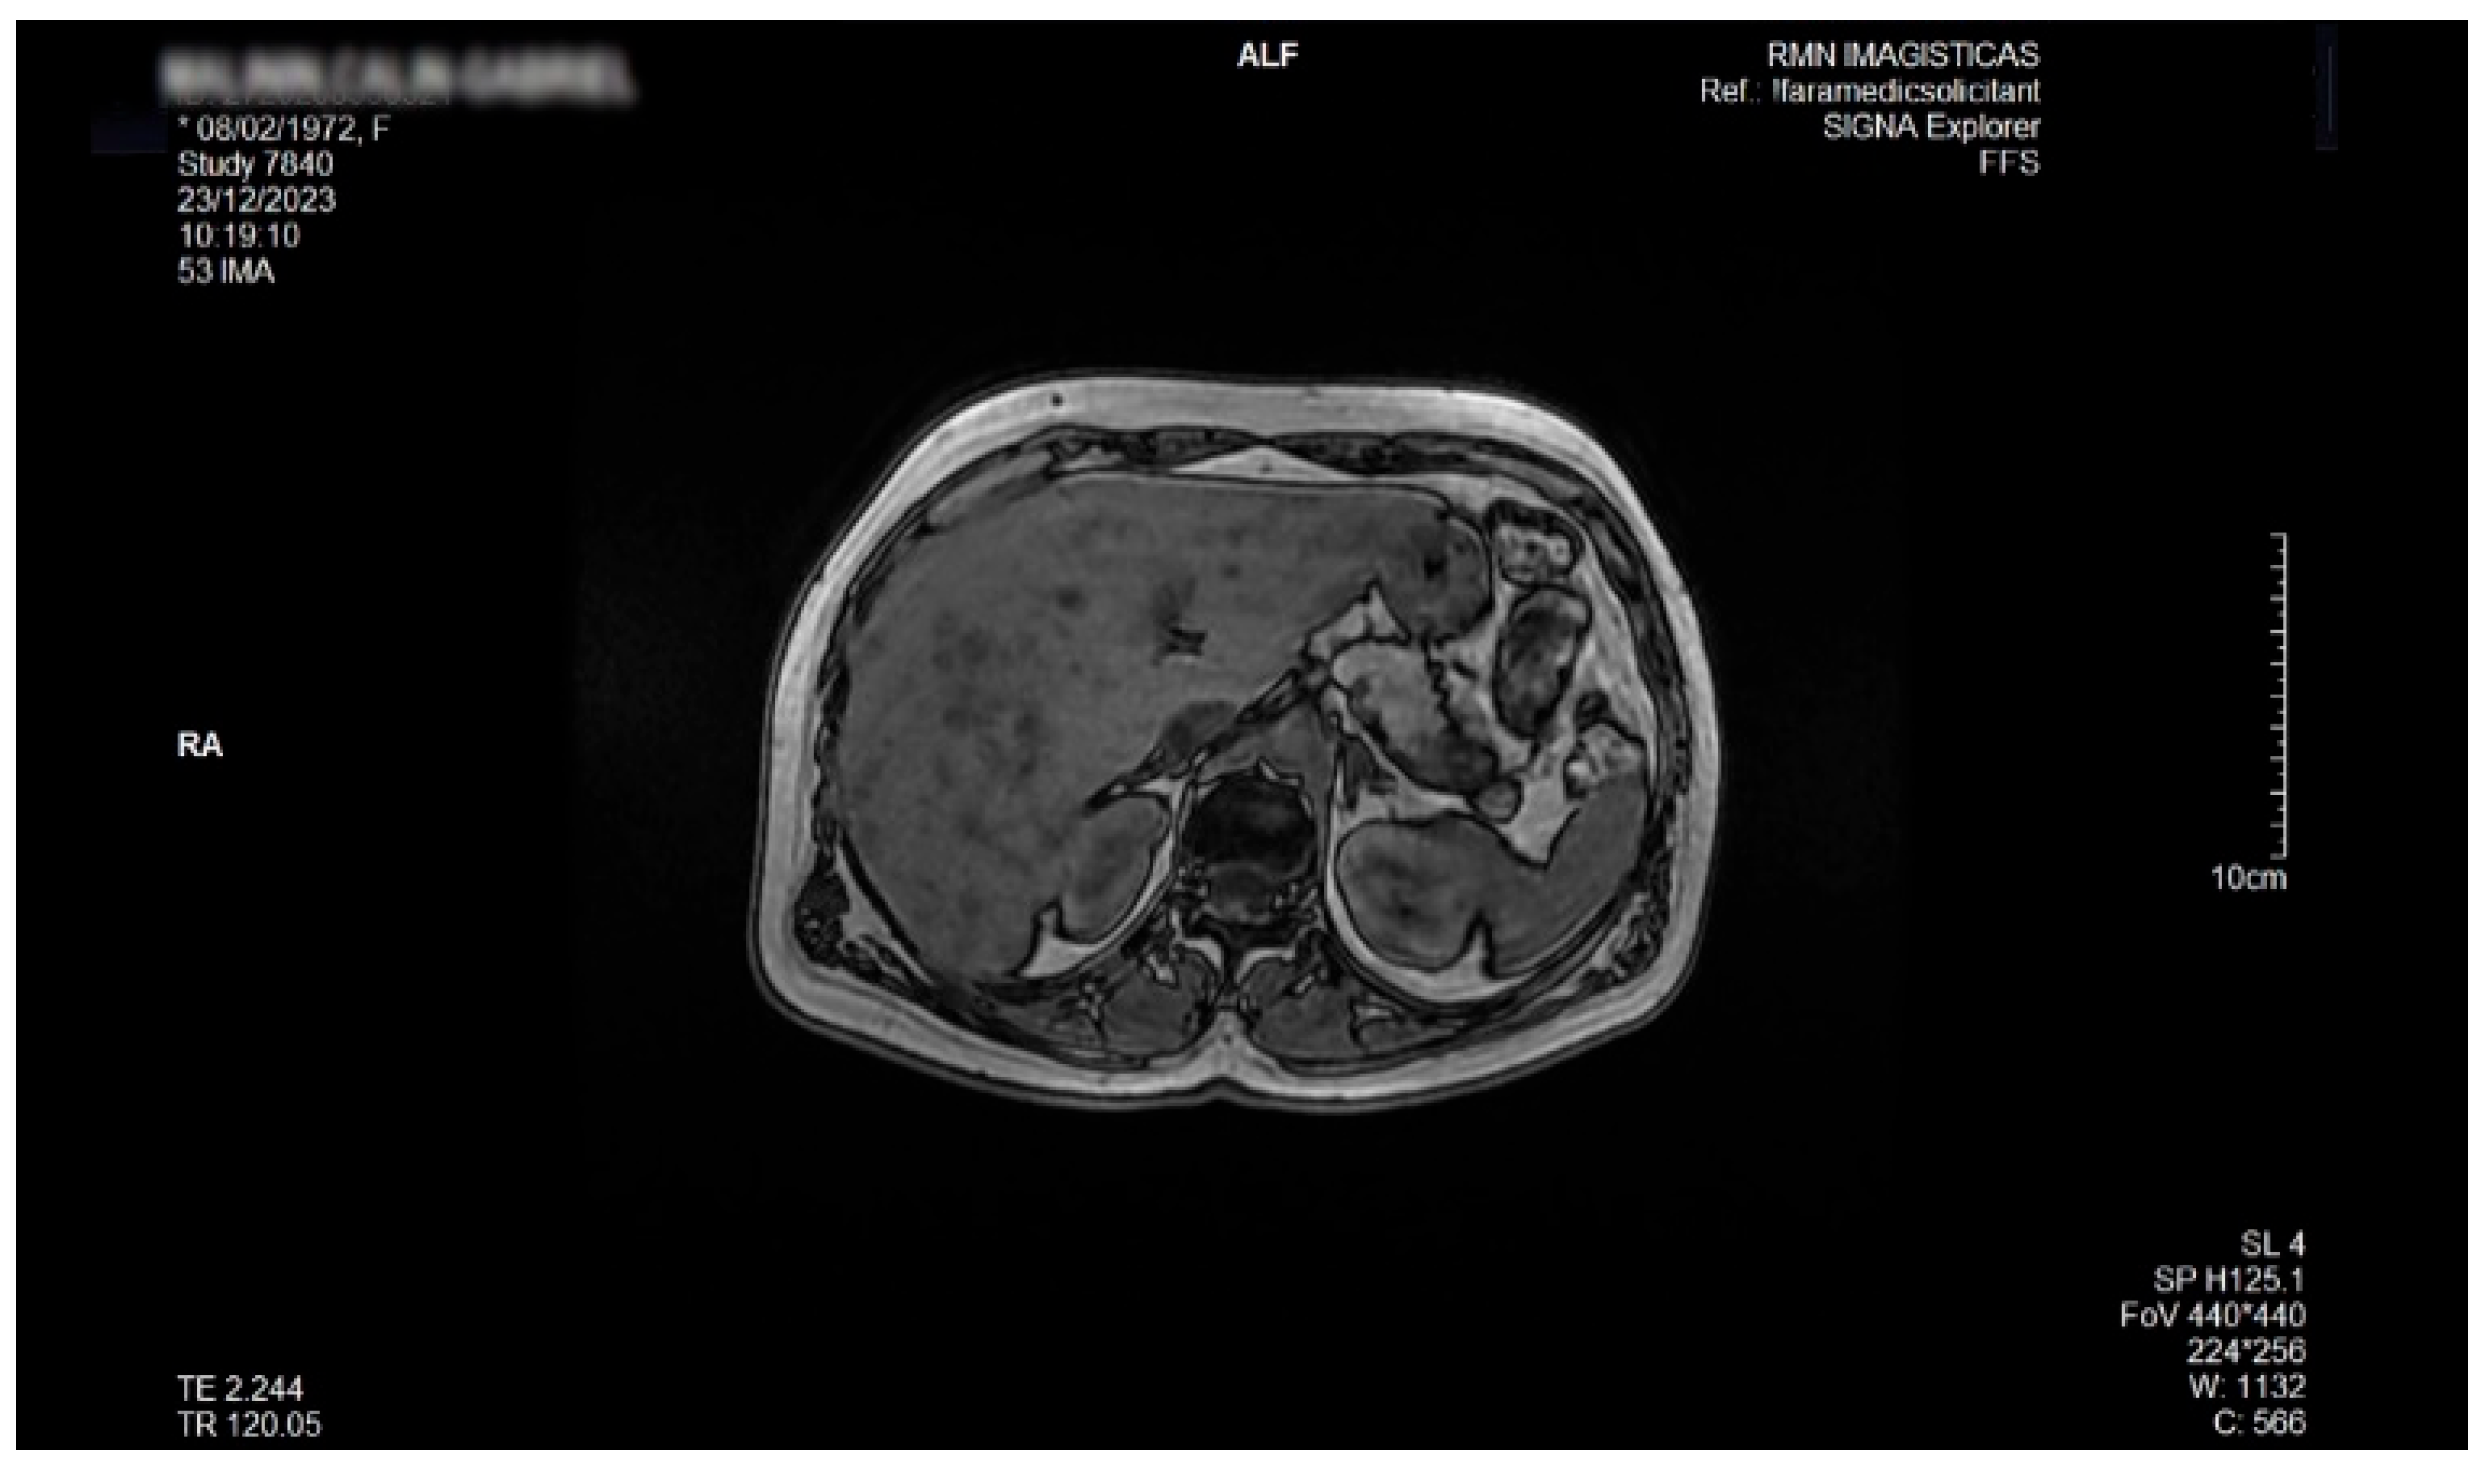

Detailed Case Description